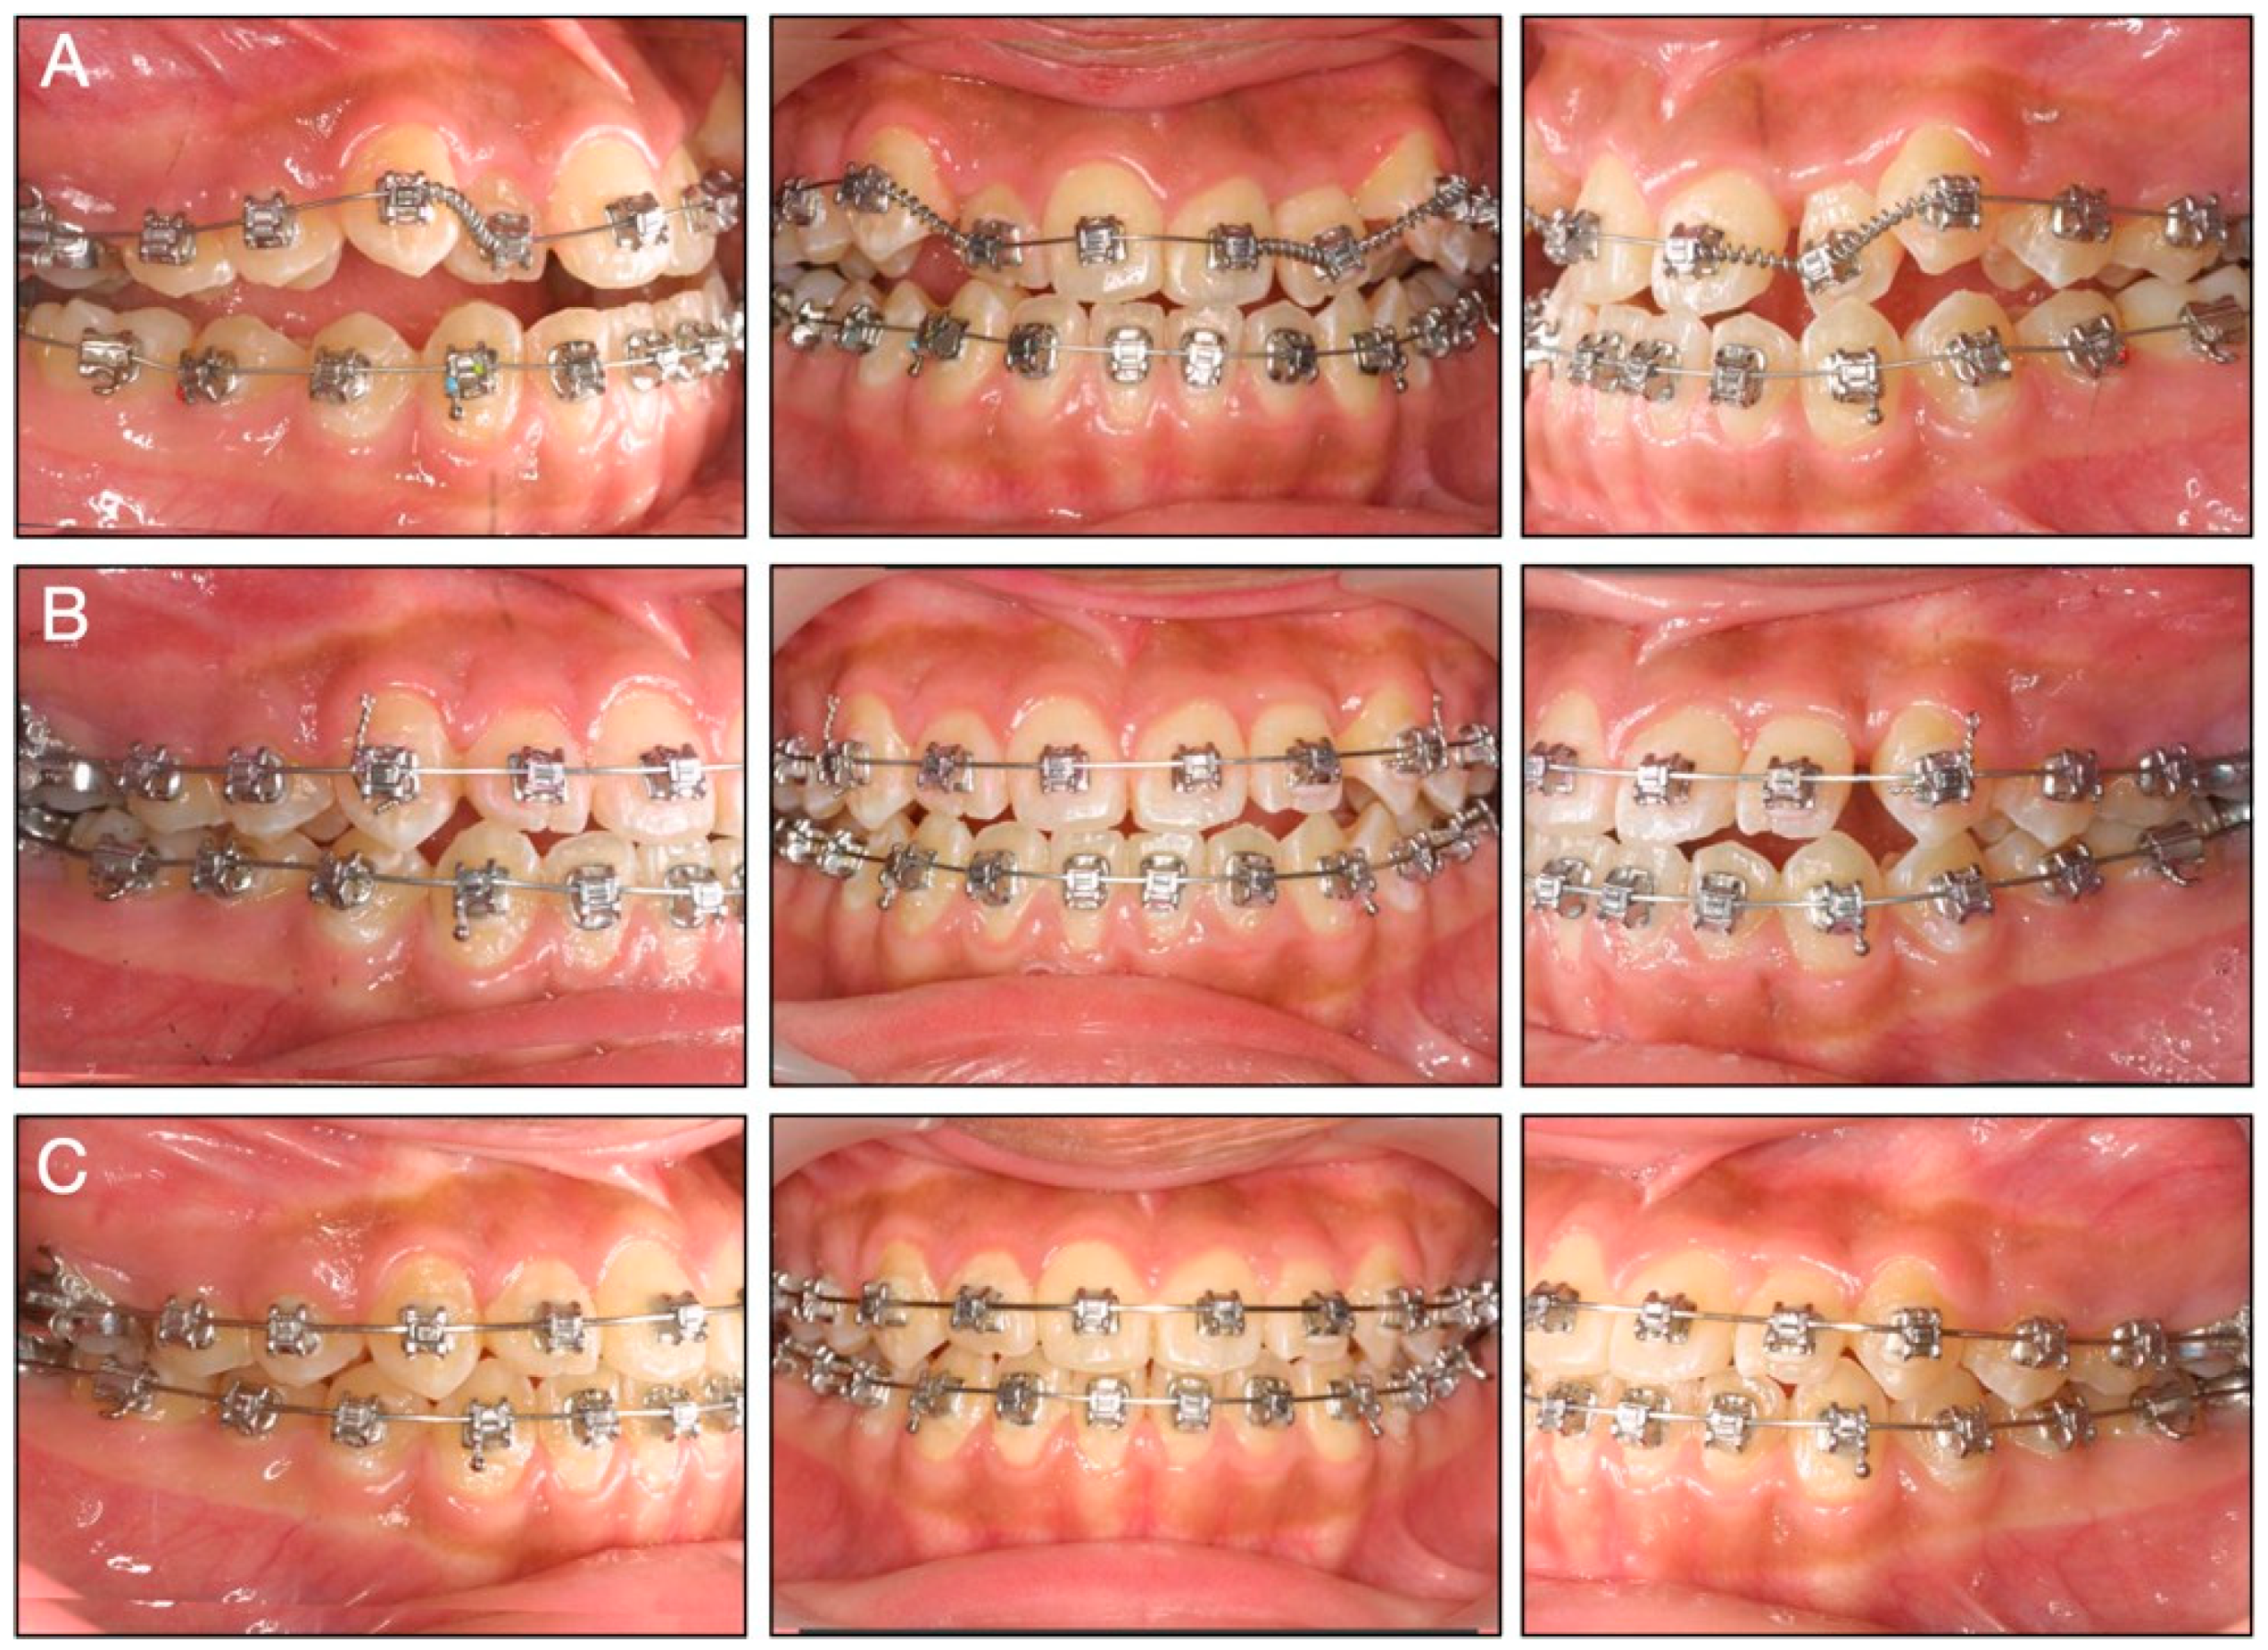

2.4. Treatment Progress

2.5. Treatment Results